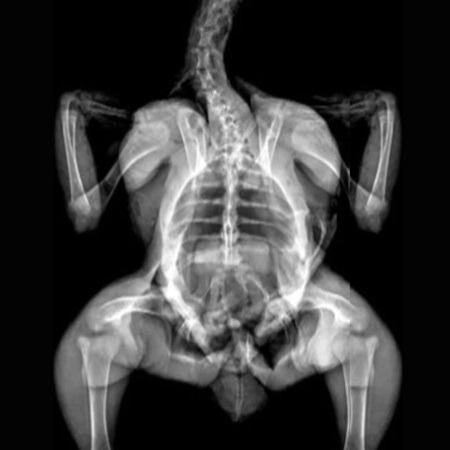

Color Image - Rat. Image Credit: Scintica Instrumentation Inc

The iNSiGHT technology employs dual energy X-rays to provide highly accurate and repeatable body composition assessments. The system categorizes each pixel into one of three compartments: fat mass, non-bone/lean mass, or bone mineral content, and provides measurements such as bone mineral density, bone mineral content, bone area, tissue area, fat tissue percentage and weight, lean tissue percentage and weight, and total weight in grams.